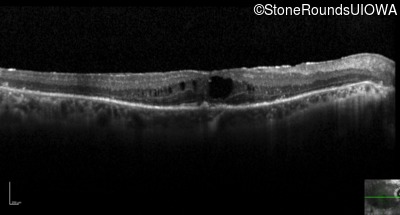

Optical Coherence Tomography - Left - 20/125

Exemplar / OCT Stack

OCT Stack